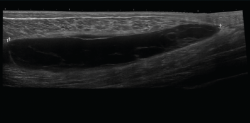

El ultrasonido se puede usar en el diagnóstico de numerosas patologías y puede guiar en procedimientos diagnósticos y terapéuticos(5).

Su indicación fundamental es en el diagnóstico de las lesiones de partes blandas superficiales.

Las estructuras específicas más adecuadas para este estudio incluyen tendones, músculos y ligamentos, además de masas periarticulares de tejidos blandos. Es útil para el diagnóstico de derrame articular, engrosamiento sinovial, bursitis, cuerpos libres intraarticulares, gangliones, quistes, roturas ligamentosas y tendinosas, tendinitis y fracturas ocultas(6).

En el estudio musculoesquelético se utiliza una sonda lineal con alta frecuencia, de entre 9 y 13 mHz.

2.2. Roturas

Se observan áreas hipoecoicas de solución de continuidad de las fibras tendinosas(7), con retracción de los márgenes con la contracción muscular cuando la rotura tendinosa es completa (Figuras 9 y 10).

Figura 9. Corte sagital de una ecografía de rodilla: foco hipoecoico por rotura parcial del tendón cuadricipital.

Figura 10. Corte sagital de una ecografía de rodilla: ausencia del tendón rotuliano por rotura completa, con hematoma señalado en el trayecto del tendón.